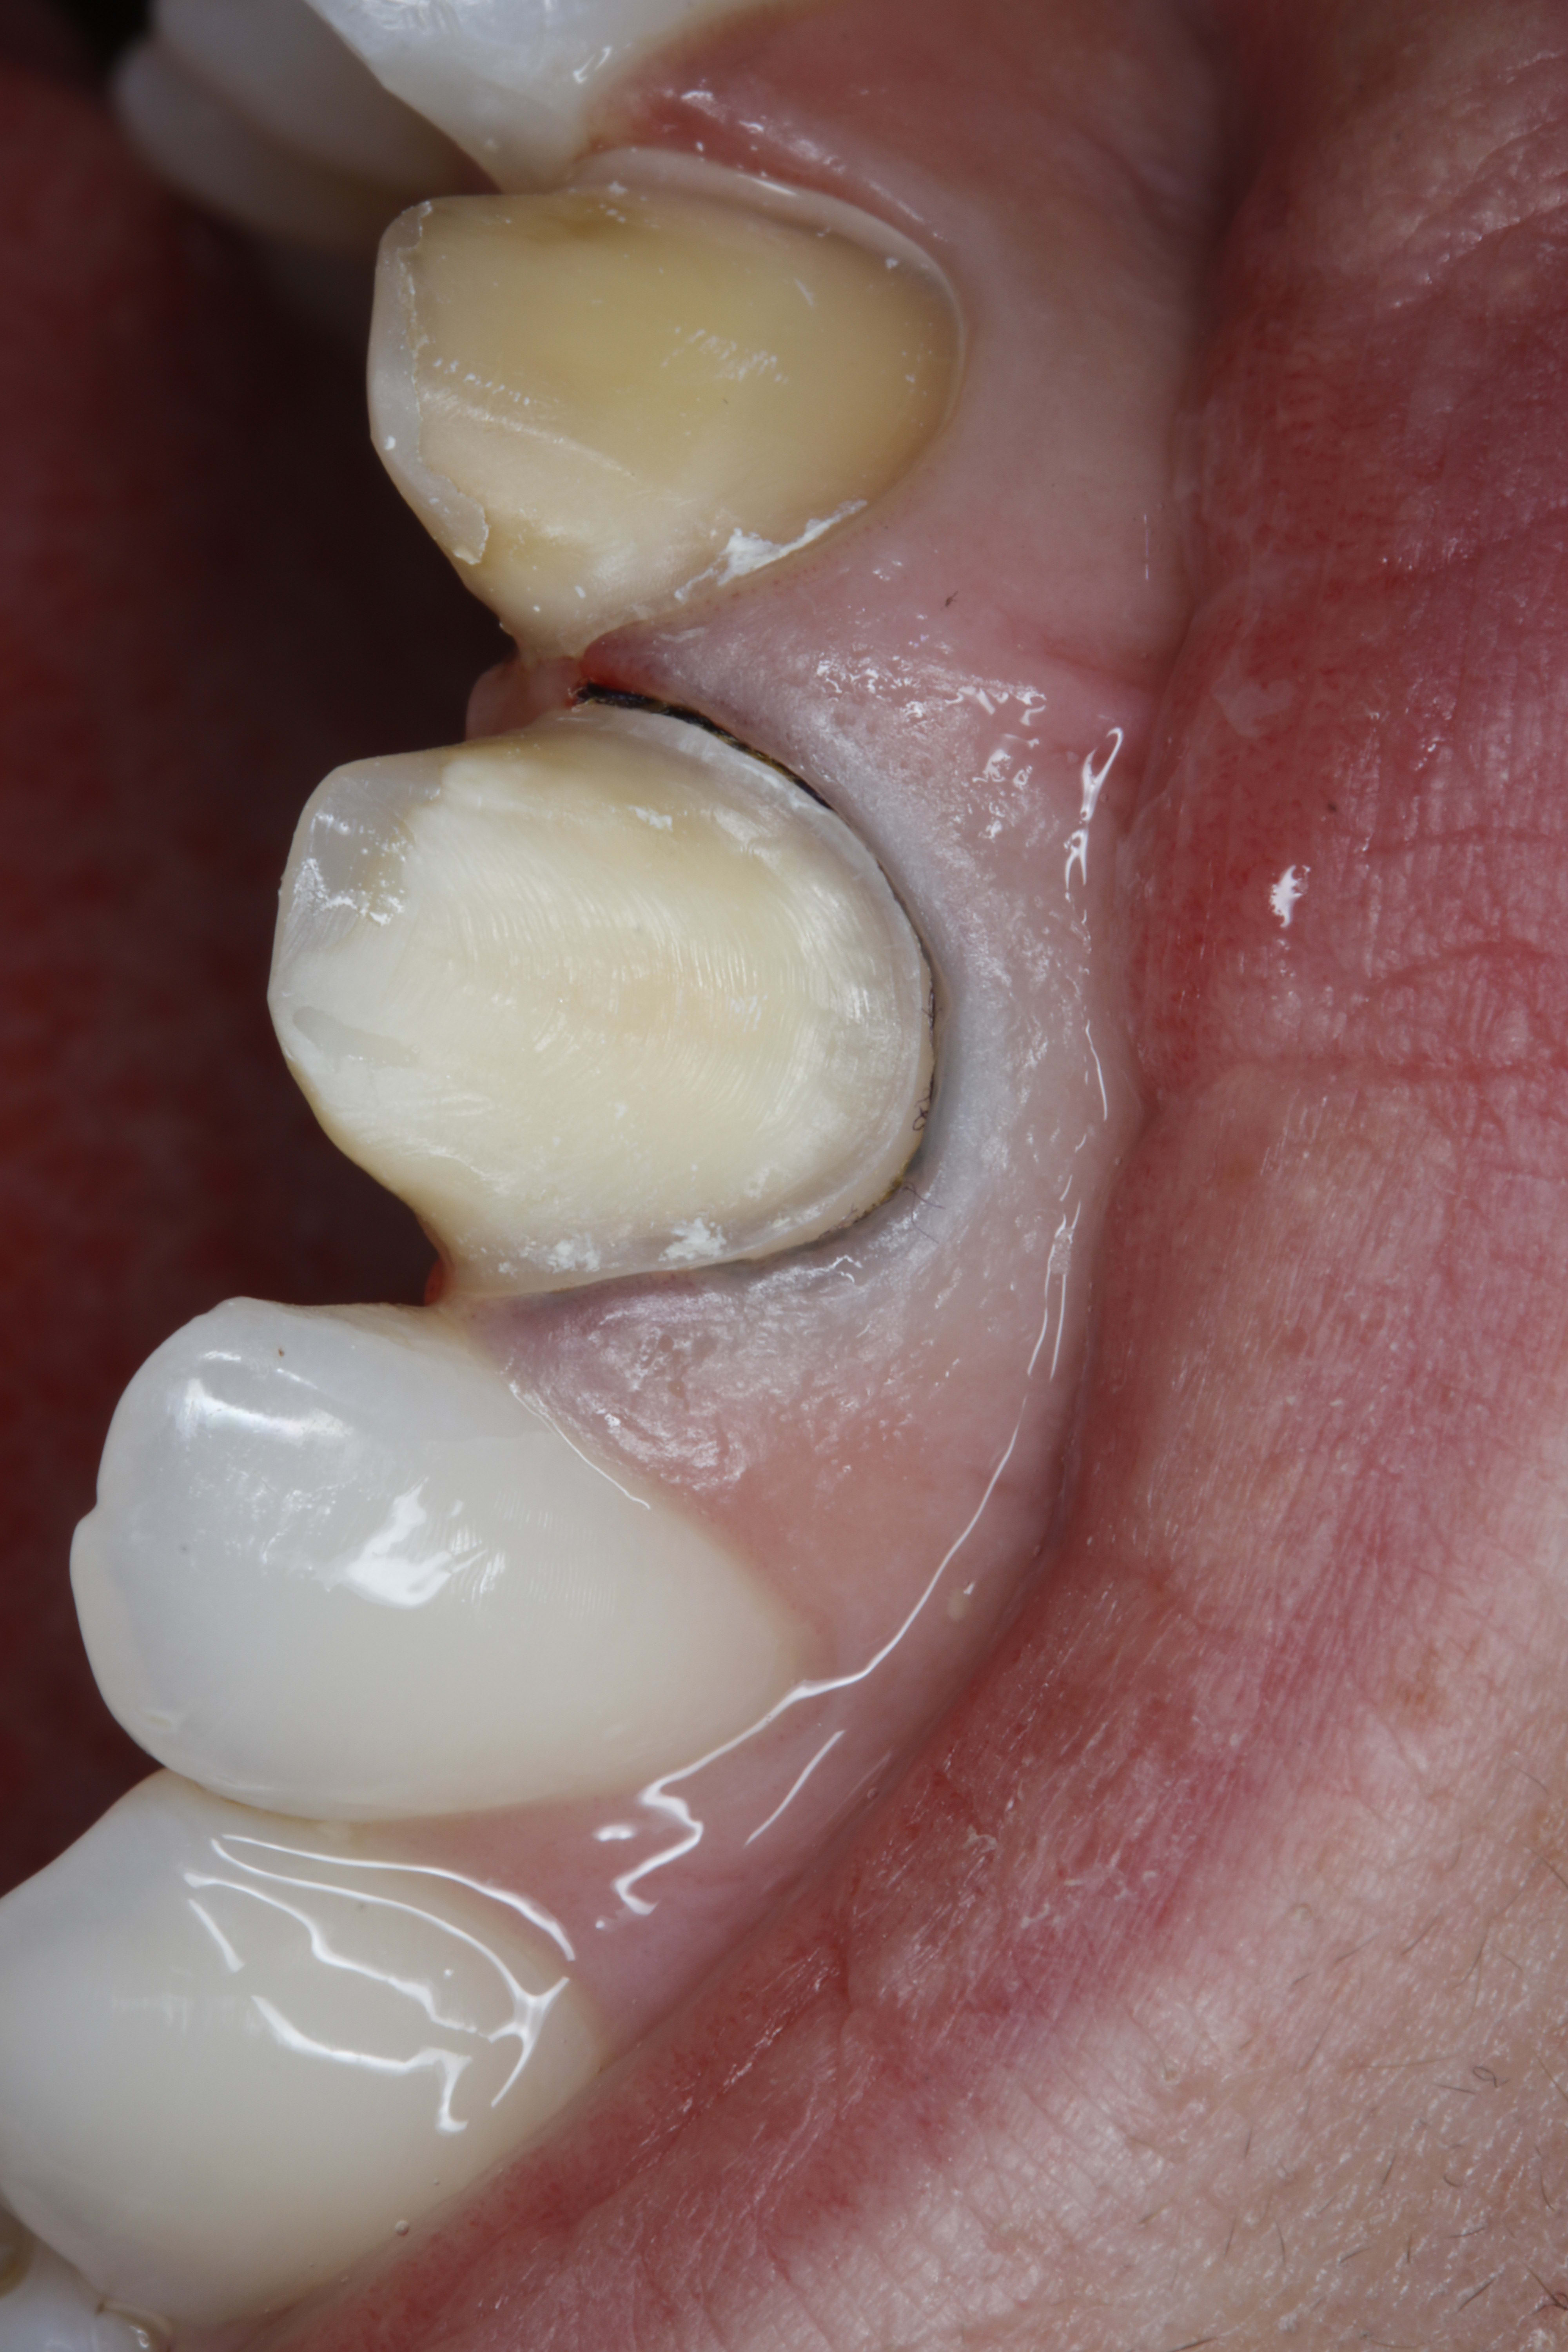

Et là c'est 13-14-15 bridge CCM ... toujours le nouveau labo spécialisé en chinoiserie que je suis en train de tester

Tu n'as plus qu'à refaire le bloc incisivo-canin de la même teinte et ce sera nickel.

Qu'est ce qu'il a le vulpi ? Il est de mauvaise humeur aujourd'hui 😊... c'est pas de la ceramo céramique... une CCM a toujours un aspect plus opaque que les ccc. Un poil de cul plus jaune si tu préfères

et celle là c'est pas de la même teinte Vulpi ? On fait moins le malin tout d'un coup. On l'entend plus le Vulpi :)) . On fait profil bas :)

La 12 était comme la 22 , donc correction de la rotation.

Pas la peine de me dire qu'il y a les composites sur les dents d'à coté à refaire. Je commence à vous connaître

Y a la 11 dépulpée qui sera couronnée plus tard (un peu plus jaune la 11)